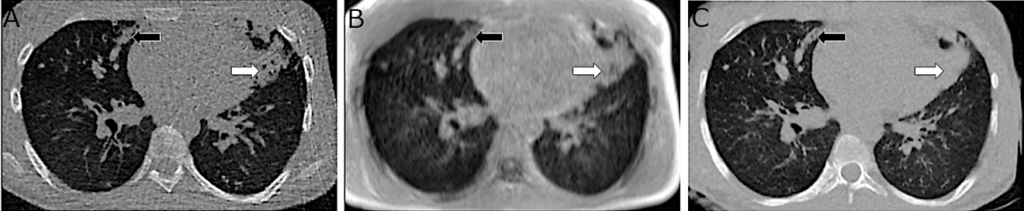

Figure 2. Example of MRI image quality enhancement enabled by AI. On the left, native CT scan; in the center, ultra-short echo time (UTE) MRI; and on the right, synthetic CT scan generated by converting MRI images into a CT-like format. Improved contour delineation, reduced artifacts, and better visibility of structural abnormalities are observed in the synthetic CT scan.